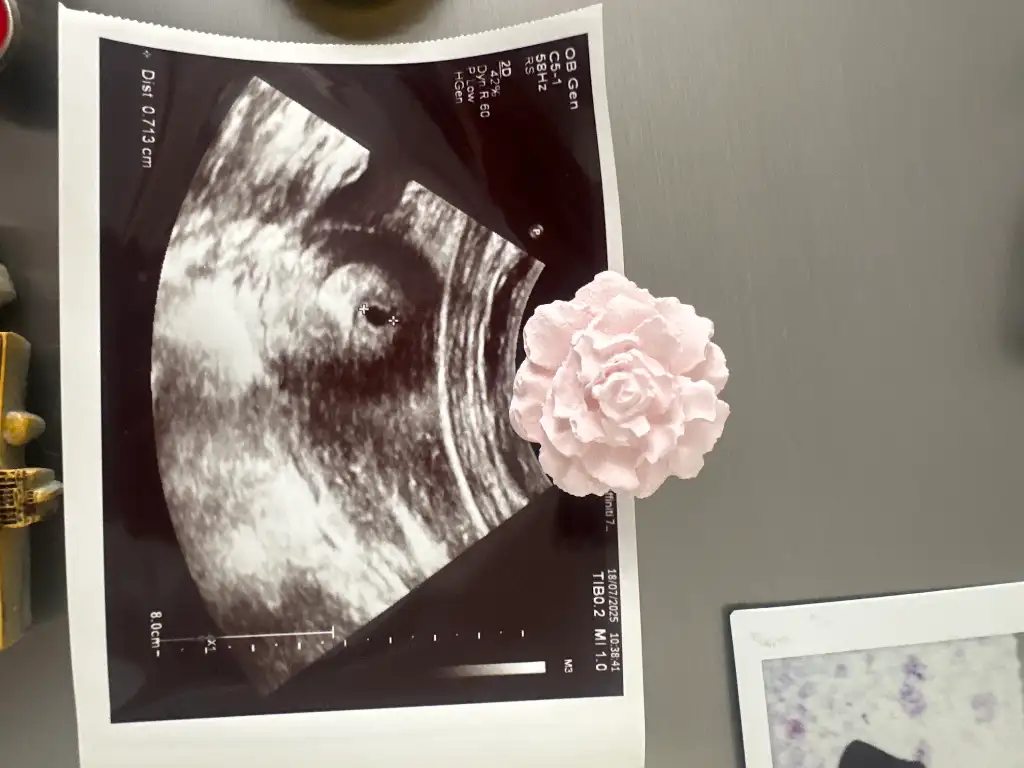

Benim 9mm demişti 5+2 de. 1 gün bile fark ediyor herhalde. Ay ne çok bilinmezlik yaBenim de 7mm miş

İlk haftalarda böyle ufak tefek sapmalar olabiliyor. Benim hesaplarima göre 6+4 olmamız gerekirken 6+1 çıktı mesela. O yüzden canını sıkma. Bir süre sonra yakalıyor zamanını. Bir de ikiz gebeligimi 10. Haftamda ögrendim. Eğer varsa senin de daha belli olmamış olabilirBence geç döllenme olamaz hatta erken bile oldu sankibilmiyorum ki haftaya daha netleşir herhalde

Chatgbt ye sordum bana embriyo 7mm dedi 6haftaliksin dedi o ortadaki minik siyah kese mi bebek miİlk haftalarda böyle ufak tefek sapmalar olabiliyor. Benim hesaplarima göre 6+4 olmamız gerekirken 6+1 çıktı mesela. O yüzden canını sıkma. Bir süre sonra yakalıyor zamanını. Bir de ikiz gebeligimi 10. Haftamda ögrendim. Eğer varsa senin de daha belli olmamış olabilir![]()

9mm olan bebek mi ben orayı anlamadımBenim 9mm demişti 5+2 de. 1 gün bile fark ediyor herhalde. Ay ne çok bilinmezlik ya![]()

Siyah şey kese. İçinde bebiş oluşuyor

ama o kadar küçük ki şuan görünemez. bir süre sonra anca görünür

9 mm kesenin çapı. Bebek daha görünmediği için kese ölçülüyor9mm olan bebek mi ben orayı anlamadım![]()

Anladım9 mm kesenin çapı. Bebek daha görünmediği için kese ölçülüyor![]()

Kese kuşum onu yazmamışım afedersin9mm olan bebek mi ben orayı anlamadım![]()

Bana doktor dedi, benim de kullandığım uygulamaya göre aynı gösteriyor. İkisi de 5+6 Uygulama son adet tarihini baz alıyor, doktor da aslında son adet tarihini baz alıyor. Kesenin ölçüsüne göre yorum yapıyor. Eğer kese boyu daha küçük ya da daha büyükse ona göre tahminde bulunuyor. Bu bebekte bir sorun olduğu ile ya da çok daha iyi gittiği ile ilgili değil. Kullandıkları cihazın kalitesine, doktorun tecrübesine, geç ya da erken döllenme vs ile ilgili olabiliyor. Ama bence en önemlisi cihazlar. Gelişmiş hastanelerde cihazlar çok daha iyiKızlar size tam gününü doktor mu söylüyor 5+2 vs diye yoksa internetteki tahminler mi çünkü bana direk 4 hafta dedi gününü falan söylemedi yarın 5 oluyor hesaplamalarıma göre

Sizin çok normal gidiyor endişe etmeyin. Aramızda 1 hafta var, geçen hafta ile aynı ölçülerimiz. Sorun var gibi düşünmeyin canınızı sıkmayınBenim de 7mm miş

O siyah şey kese, bakın benim de bugün kesemin içinde bebişim göründü pirinçten küçük dedi doktorChatgbt ye sordum bana embriyo 7mm dedi 6haftaliksin dedi o ortadaki minik siyah kese mi bebek mi![]()